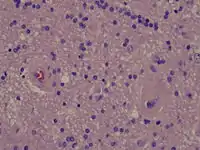

Radiation necrosis

- Brain Radiation Necrosis

Intermediate power microscopy